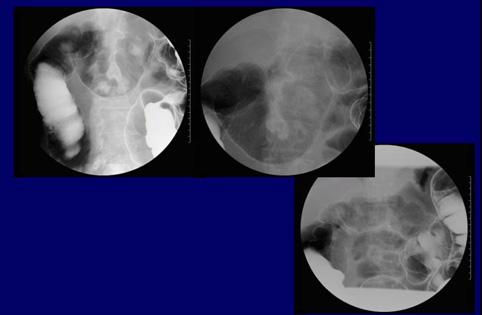

A case of idiopathic mesenteric phlebosclerosis (phlebosclerotic colitis).

염증성 및 궤양성질환/정맥경화성 대장염

대장/2구역 이상의 대장에 걸치는 것

X-P